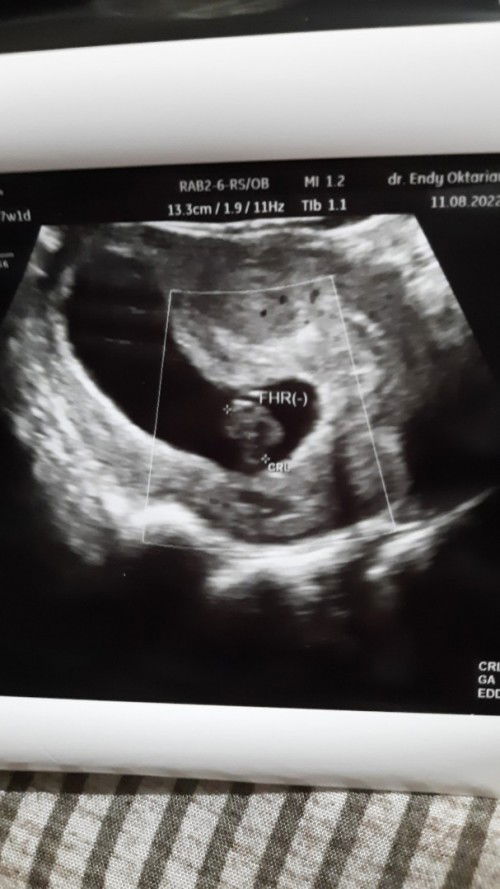

Bun usia kandungan saya saat ini 7week masuk 8 week. Seminggu yang lalu saya usg ke dokter kandungan janin udah ada detak jantung dan berkembang dengan baik. Lalu karna saya mual dan muntah cukup parah akhirnya memutuskan konsultasi ke dokter kandungan yang beda dari sebelumnya. Saat di USG 2D, dokter kandungan yang kedua ini memvonis janin dalam kandungan saya sudah meninggal karna detak jantungnya gak ada. Karna kurang yakin akhirnya di lakukan pengecekan USG Transvaginal dan hasilnya sama detak jantung gak terdeteksi. Dokter menyarankan untuk segera di lakukan kuret. Tapi saya masih gak yakin karna saya gak ada keluar flek atau keram perut. Kalo bunda ada yang punya pengalaman serupa tolong bagi pengalamannya bun tindakan apa yang harus di lakukan. #bantusharing #pleasehelp